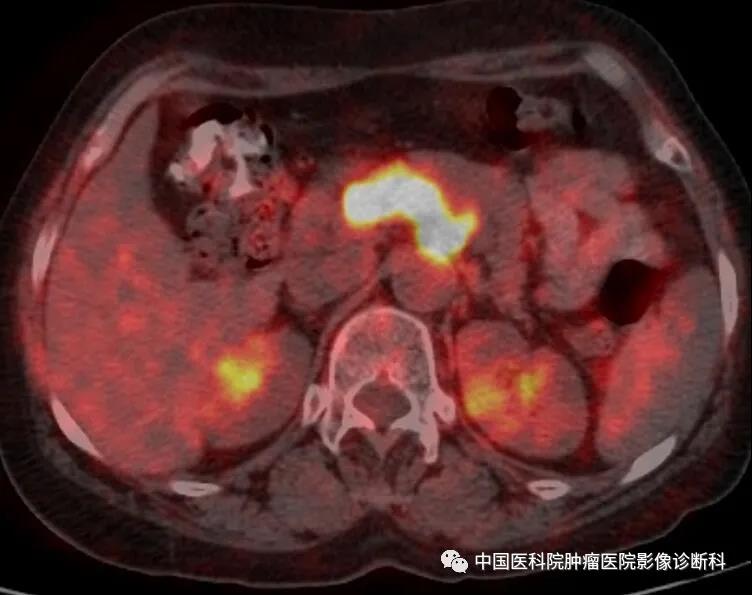

腹部PET-CT融合图(腹膜后病灶最大SUV:18.5)